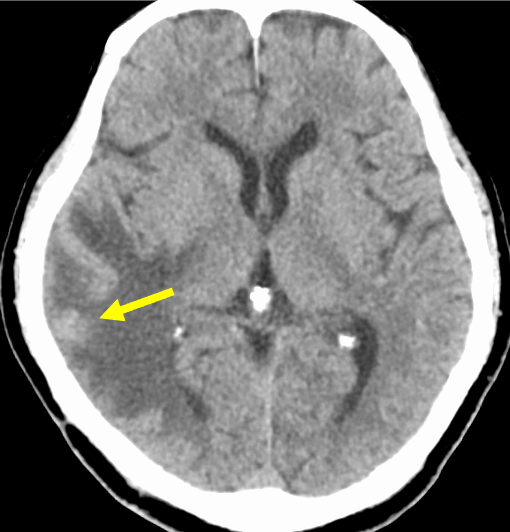

図1.単純CT

右側頭葉皮質下白質に灰白質とほぼ等吸収な腫瘤と周囲に広範な浮腫を認めた。